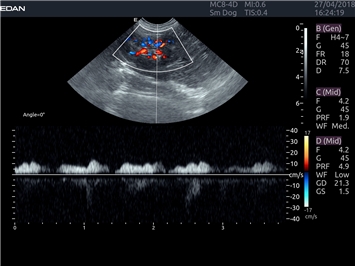

EDAN Acclarix LX4 VET представляет собой профессиональную ультразвуковую систему, специально разработанную для ветеринарных исследований. Сочетание стабильности, высокой производительности и эффективности делает эту систему идеальным выбором для современной ветеринарной практики.

Инновационные технологии обработки изображений:

• Адаптивная визуализация тканей:

• Оптимизация изображения для различных видов животных

• Улучшенная детализация структур

• Мультилучевое сложно-составное сканирование (SCI):

• Повышенная четкость изображения

• Улучшенная визуализация сложных анатомических структур

Цветовой допплер:

Да

Импульсно-волновой допплер: